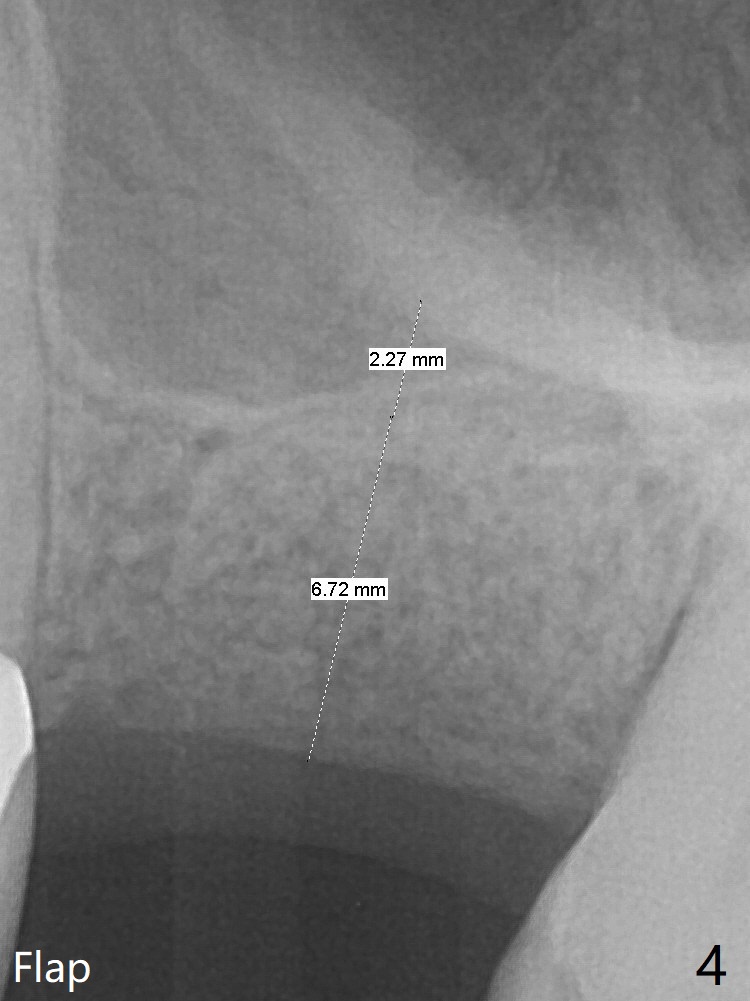

A 61-year-old woman has pain after RCT at #14 (Fig.1). Exam shows subgingival crack. After difficult extraction, allograft with Osteogen is placed in the 3 sockets, followed by Osteogen plug and 4-0 Chromic Gut Suture. The distal gingiva appears to be migrating into the center of the sockets (Fig.2 arrow). Due to insurance issue, an implant will be placed early next year. The patient returns 9 months post extraction (Fig.3). If the ridge proves to be not so wide, make incision, start osteotomy with 1.6 mm pilot drill, followed by 4.3 mm Magic Drill for 7 mm and 3.8 mm Magic Expander for another 2 mm (sinus lift, BEB, Fig.4). Otherwise start Magic Split. If the bone is dense, use drills and Expander as mentioned above with the depths 2 mm more (Fig.5), followed by Magicore. The tissue-level implant improves the crown/implant ratio over the FC. After socket healing, gingival cuff height is stable. The cuff of Magicore is easy to determine vs. immediate case.